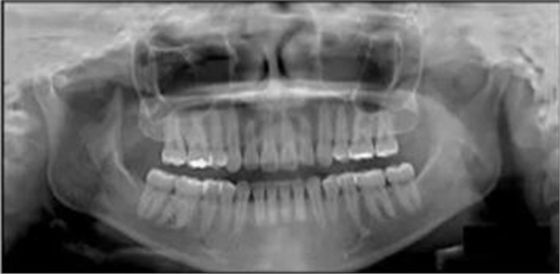

3.測(cè)量分析:治療前記錄提示該患者左右磨牙與尖牙為安氏II類關(guān)系,上頜牙弓重度擁擠,下頜牙弓輕度擁擠,深Spee曲線。6.3mm深覆蓋,80%深覆合。牙齒無(wú)齲,無(wú)第三磨牙。

頭側(cè)分析提示為骨性安氏II類(ANB,8.4°;Wits,3.6mm),高角(SN-MP,44.9°),上頜切牙略舌傾(U1-SN,96.2°),下頜切牙略舌傾(IMPA,88。3°)(圖2;表)

治療后全景片提示間隙得到關(guān)閉,除了左下頜第一前磨牙外牙根平行度可,無(wú)明顯骨及牙根吸收。(圖7)